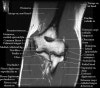

팔꿈치 관절의 MRI 단면 영상

4. MR Arthrography : Useful for evaluation of the collateral ligaments and cartilage surfaces.

5. Elbow Arthrography : UCL pathology in throwers, Osteochondral lesions and repair, Loose bodies